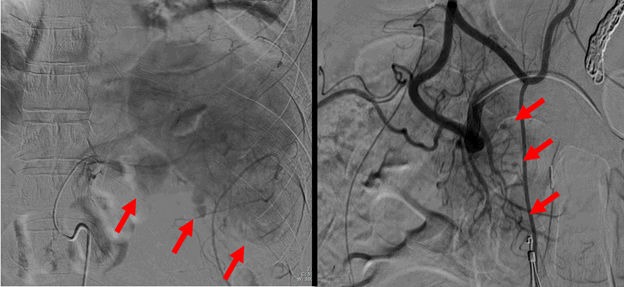

A 46-year-old male with a past medical history of recurrent, mild acute pancreatitis and prior cholecystectomy presented to the emergency room with abdominal pain radiating to the back, nausea, and vomiting. Lab work was remarkable for a serum lipase of 11,420 U/L and serum hemoglobin of 15.4 g/dL. Contrast-enhanced computed tomography (CECT) confirmed acute interstitial pancreatitis. A two-week hospital admission was required for supportive care, during which a repeat CECT demonstrated progression to necrotizing pancreatitis (NP) with an acute necrotic collection. Less than twenty-four hours after discharge, the patient was readmitted with worsening abdominal pain, nausea and vomiting, and poor oral intake. Repeat CECT revealed two new peripancreatic hematomas near the body and tail of the pancreas that measured 9 and 5.5 cm, respectively. Additionally, four sites of active bleeding were identified; three along the body/tail of the pancreas and one at the head of the pancreas (Figure 1). The patient was urgently transferred to our hospital for further management.

Figure 1. Visceral artery pseudoaneurysms (arrows) within larger peripancreatic hematomas